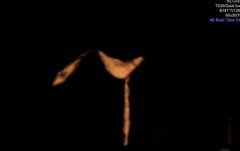

输卵管造影不一定要“吃”射线!我院全市首开子宫输卵管超声造影术

无辐射、检查完当月即可备孕、准确性高,近日,济宁市第一人民医...